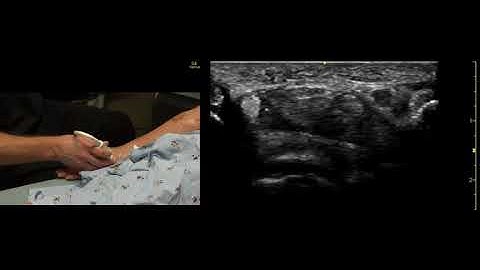

Identifying the Radial Nerve for POCUS Guided Regional Anesthesia